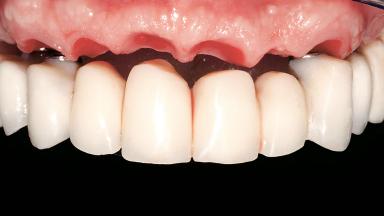

Immediate Loading of Six Implants in the Maxilla and Final Restoration with a Full-Arch CAD/CAM Zirconia FDP

A 63-year-old male patient was referred for a consultation and treatment of partial edentulism in the maxilla. The patient presented with residual anterior teeth and declined a partial removable prosthesis. He reported that the maxillary posterior teeth had been extracted due to mobility and periodontal disease two months before the consultation. The patient’s chief complaint was that his residual maxillary teeth were mobile and that he was unable to chew. The patient’s desire was a stable and comfortable fixed maxillary rehabilitation. The patient was a light smoker (fewer than 10 cigarettes/ day), and his medical history was without significant findings. He was not on any regular medication at the time of consultation. The extraoral examination revealed a normal physiognomy with a correct distribution of the facial thirds. The patient presented a low lip line, and the transition line between teeth and soft tissues was not exposed during a forced smile.

Prosthesis Type FDP